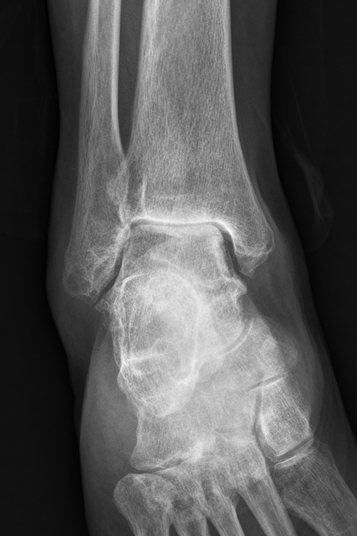

术前右踝关节片

据了解,邓阿姨右踝关节持续疼痛、活动受限、行走困难两个月,在外院治疗但效果不佳,遂至我院骨科一区就诊。入院后完善相关检查,诊断为“右踝关节创伤性关节炎”。骨科一区主任万富贵带领科室关节组团队成员开展术前讨论,为最大程度地改善患者的踝关节功能,提升患者生活质量,在与邓阿姨充分沟通后,最终决定进行既能消除疼痛、又能保留踝关节活动度的踝关节置换术。